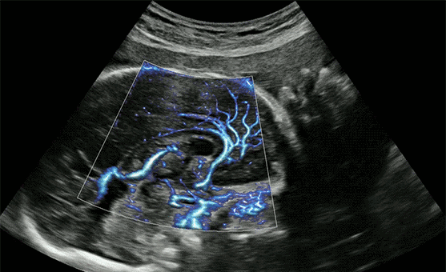

CrystalLive?是三星最新的超聲成像引擎,同時增強了2D圖像處理能力、3D渲染能力和彩色信號處理能力,能夠在復雜情況下提供出色的圖像性能,具備檢測外周血管、微循環(huán)血流的能力。

最后,展示一下該機型可搭載的探頭~目前該產品三星本土韓文官網尚未展示,僅能在英文網站查到有關信息,不知何時才能進入中國呢?